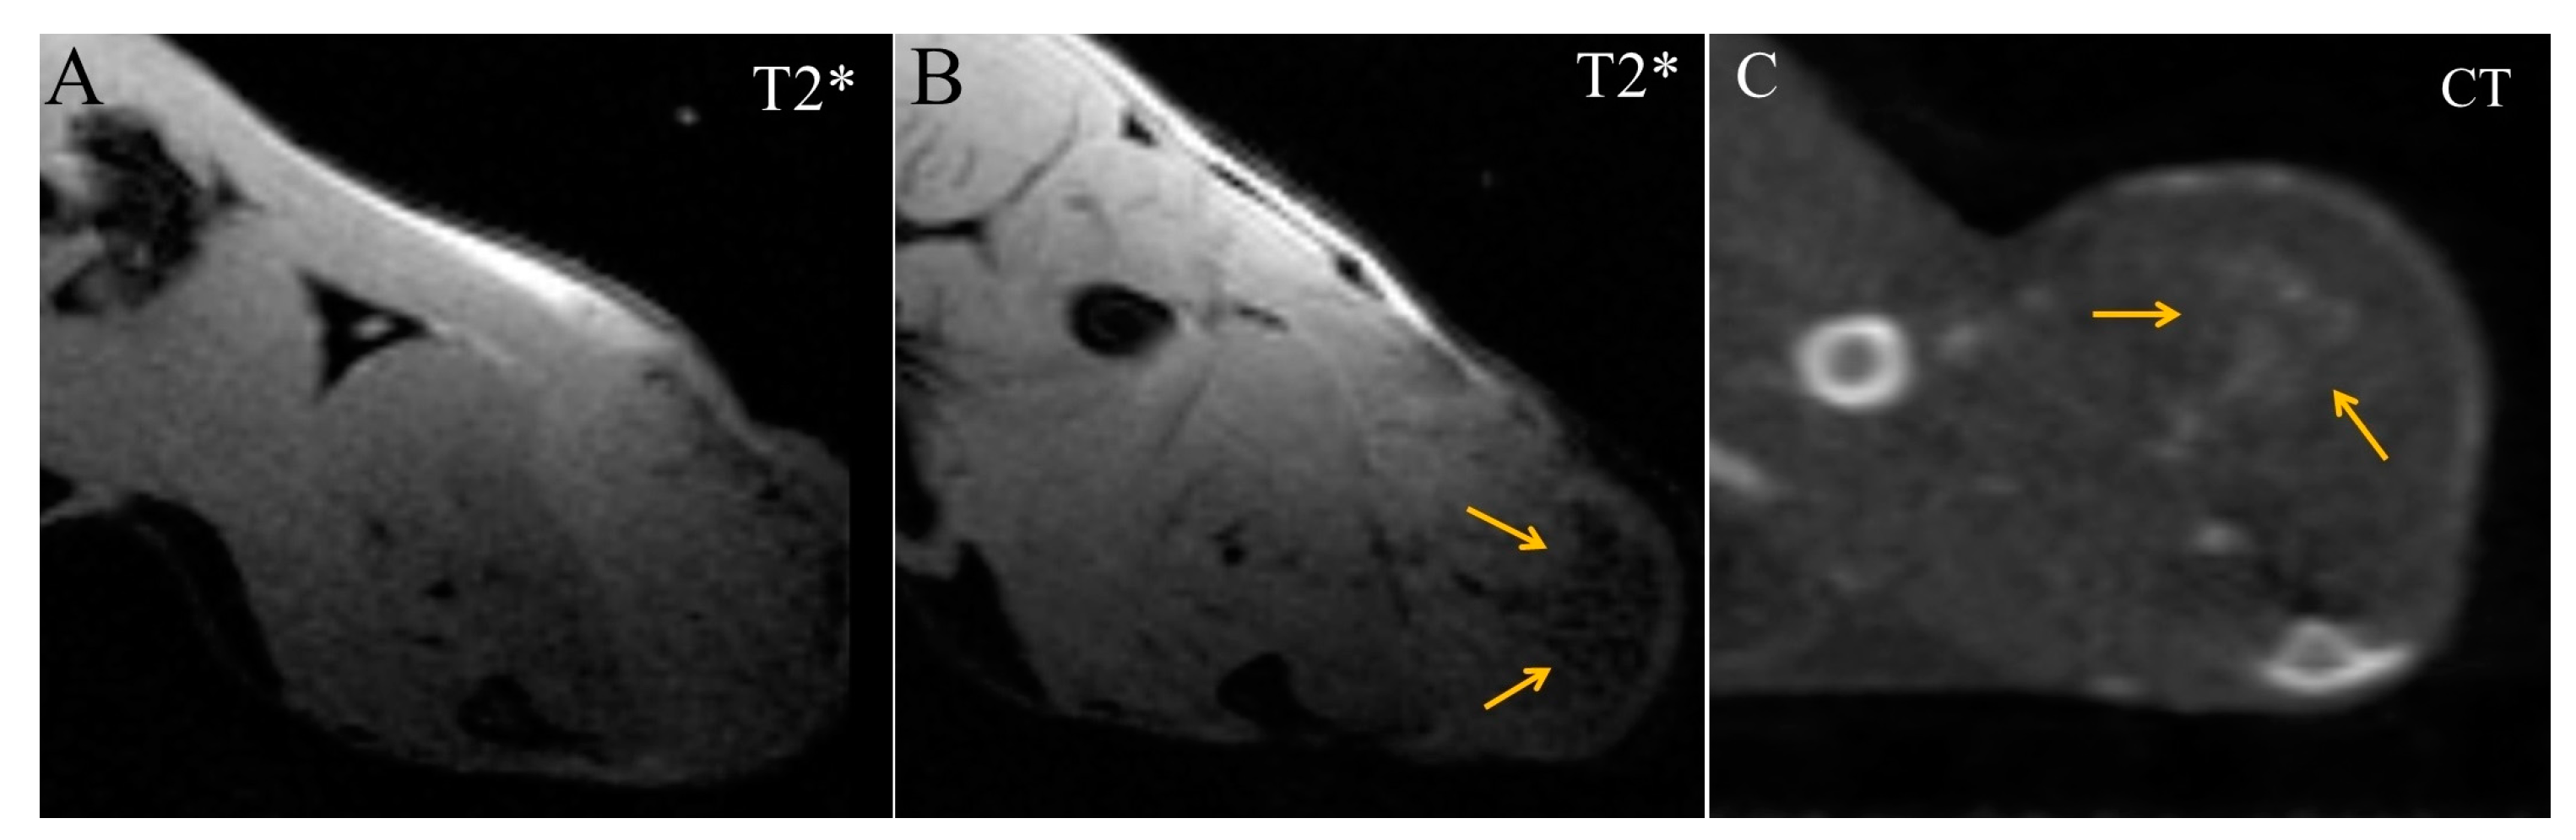

Starting from 16 min after Fe3O4@Au administration, diffuse regions of moderate enhancement appeared in the CT and MRI images of the tumor (Figure 5). They were T2*-hypointense in MRI scans but could be more precisely visualized in CT images as a triangular-shaped hyperdense zone.

Figure 5.

Transversal images of Ca755 mammary carcinoma. (A) native T2* MRI; (B) T2* MRI 16 min post injection of Fe3O4@Au; (C) CT image 22 min post injection of Fe3O4@Au. Arrows mark a triangular-shaped area of accumulation.

Tumor blood vessels were enhanced and clearly distinguished in both imaging modalities (Figure 6). The enhancement was seen not only in large nutrient vessels but also in small convoluted vessels inside the tumor. CT allowed more detailed imaging of tumor vasculature using the Fe3O4@Au bimodal nanoparticles.

Figure 6.

Transversal images demonstrate the enhancement of blood vessels. (A) T2* MRI 16 min post injection of Fe3O4@Au; (B) CT image 22 min post injection of Fe3O4@Au; (C) CT image of the tumor 22 min post injection of Fe3O4@Au. Arrows indicate blood vessels.